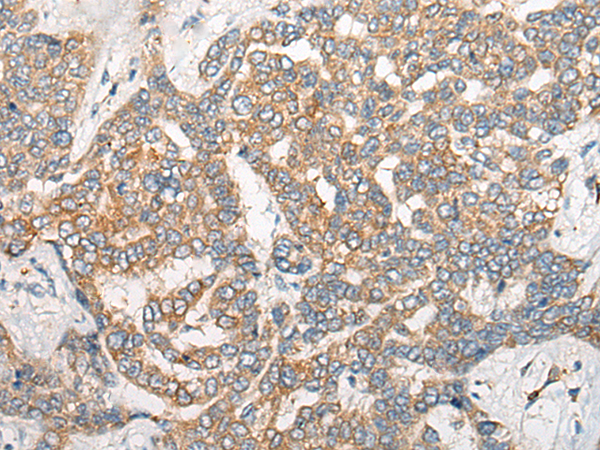

分类: 科研抗体货号: P13189别名: GAIP; RGSGAIP应用: IHC反应种属: Human, Mouse, Rat